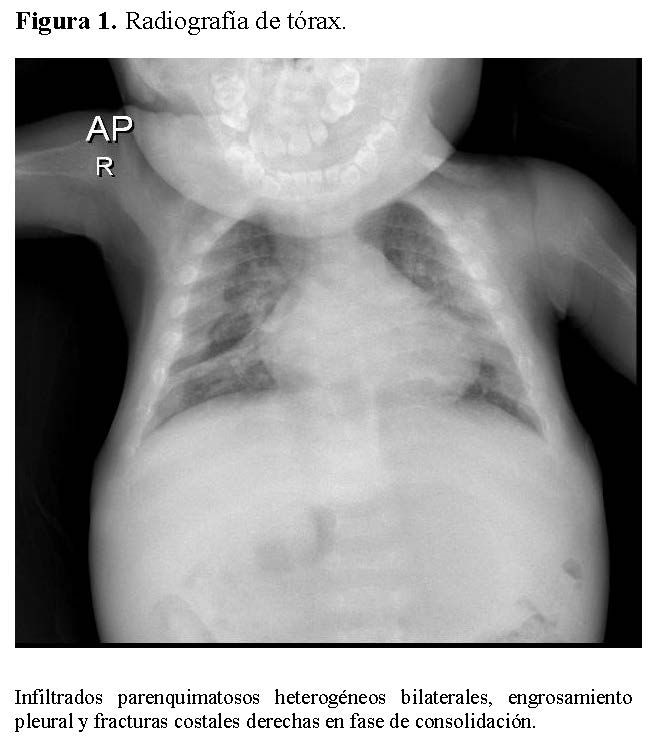

La radiografía de tórax mostró infiltrados parenquimatosos heterogéneos bilaterales, engrosamiento pleural y fracturas costales derechas en fase de consolidación (Figura 1). Las radiografías de huesos largos evidenciaron osteopenia severa, reacción perióstica y múltiples fracturas patológicas, incluyendo húmero derecho e izquierdo, cúbito derecho y fémur derecho (Figuras 2 y 3).

Figura 1.